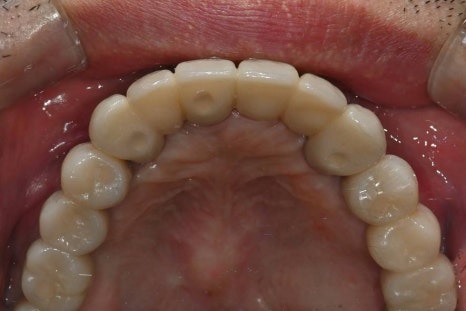

· 상악 양측 상악동 거상술 + 임플란트 10개 식립

임시치아부터 최종 보철까지의 과정

수술 직후에는

임시틀니 대신 고정형 임시치아를 적용하여

일상생활과 식사 불편을 최대한 줄였습니다.

· 수술 다음 날 임시치아 장착

· 하악 일부는 2개월 내 조기 보철 완성

· 상악은 뼈이식 안정화를 충분히 거쳐 진행

전신질환이 있어

치료 기간이 길어질 가능성도 고려했으나,

6개월 내 안정적으로

보철을 마무리할 수 있었습니다.

수술 후 4개월

수술 후 6개월 후 보철완료